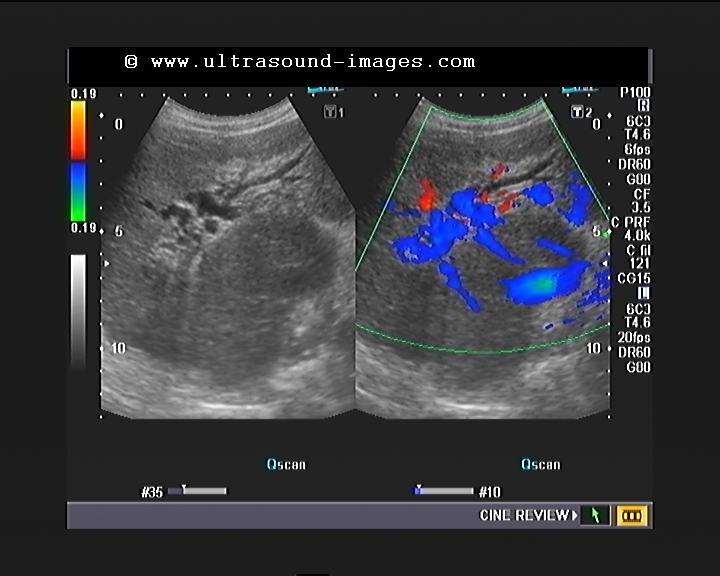

Ultrasound case study examples picture This picture representes ultrasound case study examples.

Ultrasound Case Studies The sonography case studies in this section offer you an opportunity to see a wide range of ultrasound images of normal anatomy, pathologies and anatomic variants. This can be a great resource for practitioners and students to test their knowledge and expertise in interpreting ultrasound images.